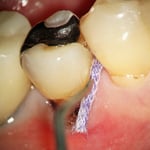

中央:歯と歯肉の境目に、圧排糸を挿入(麻酔をしてあります)します。※治療後、もちろん、圧排糸は除去します。

右図:圧排糸の効果で、歯の全面が見えてきました。左図に比べると、虫歯を除去したり、プラスティックを充填する範囲が極端に違ってくることがわかります。